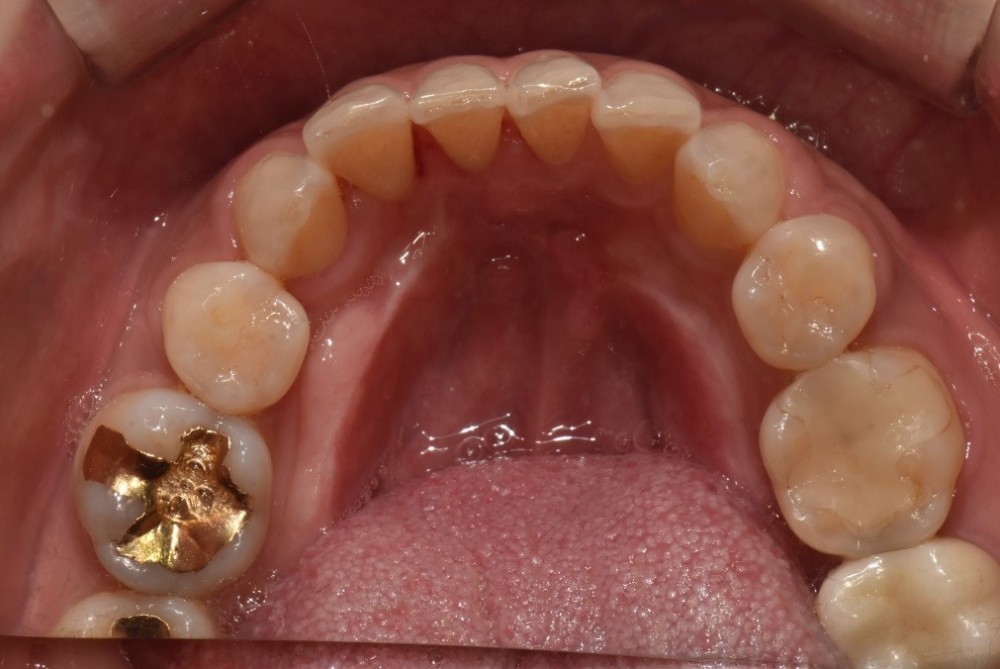

골 치즐이란 기구를 사용하여 골융기 분리 제거술을 진행하는 과정입니다.

가장 첫 번째 사진과 비교해오면 그 차이점이 눈으로도 분명하게 확인이 되실 텐데요. 이렇듯 골융기를 제거해주면서 실제로 발음이 좋아지셨고 식사를 할 때에도 골융기에 음식물로 인해 발생되는 상처가 예방되기 때문에 너무 편하게 식사를 하실 수 있게 되었습니다. 이런 골융기 제거는 난이도가 놓아 신중해야 하지만 이렇게 환자분들이 좋아하는 것을 보면 어렵게 제거한 보람이 있었다고 생각이 듭니다.